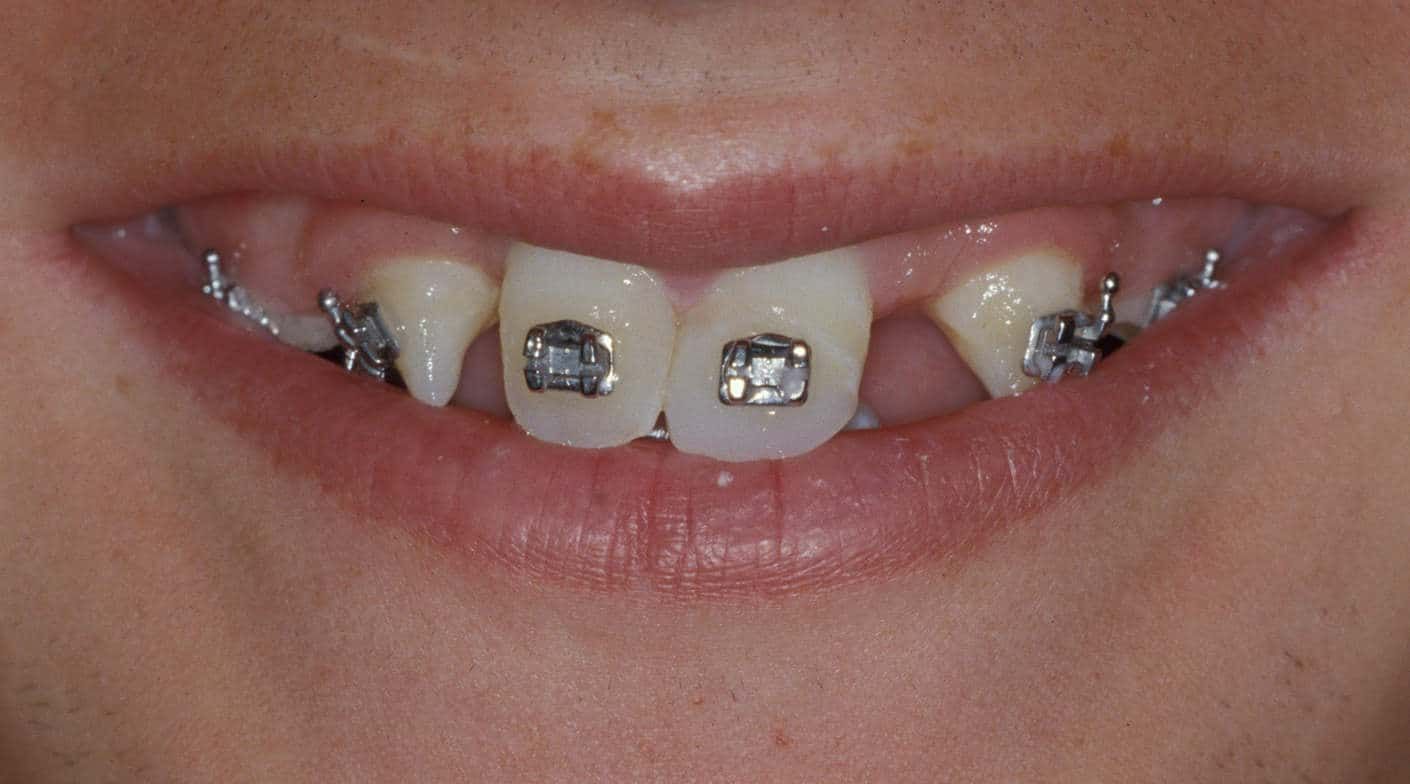

Before: Patient is missing 19 adult teeth. Treatment to replace the missing teeth began at age 12 and was completed at age 21. Treatment involved a team approach, with an Orthodontist, Oral and Maxillofacial Surgeon, and Prosthodontist (Dr. Leopardi) heading the team. Orthodontic therapy was performed first to move existing adult teeth to allow for implant tooth replacement therapy in missing teeth sites (tooth-implant-tooth relationship).